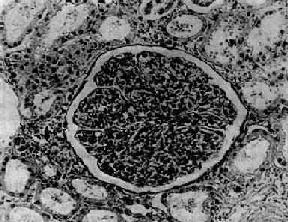

在电子显微镜下可见肾小球系膜细胞和内皮细胞增生肿胀。基底膜和脏层上皮细胞间有致密物质沉积。这些沉积物大小不等,有的很大,在基底膜表面呈驼峰状或小丘状(图12-8,图12-9)。沉积物表面的上皮细胞足突多消失。基底膜变化不明显有时边缘稍不规则。沉积物一般在发病后几天就可出现,在4~6周内消失。有时基底膜内侧内皮细胞下和系膜内也可见小型沉积物。

图12-9 毛细血管内增生性肾小球肾炎

电镜下见驼峰状沉积物位于毛细血管基底膜表面。沉积物表面有上皮细胞覆盖,上皮细胞足突消失